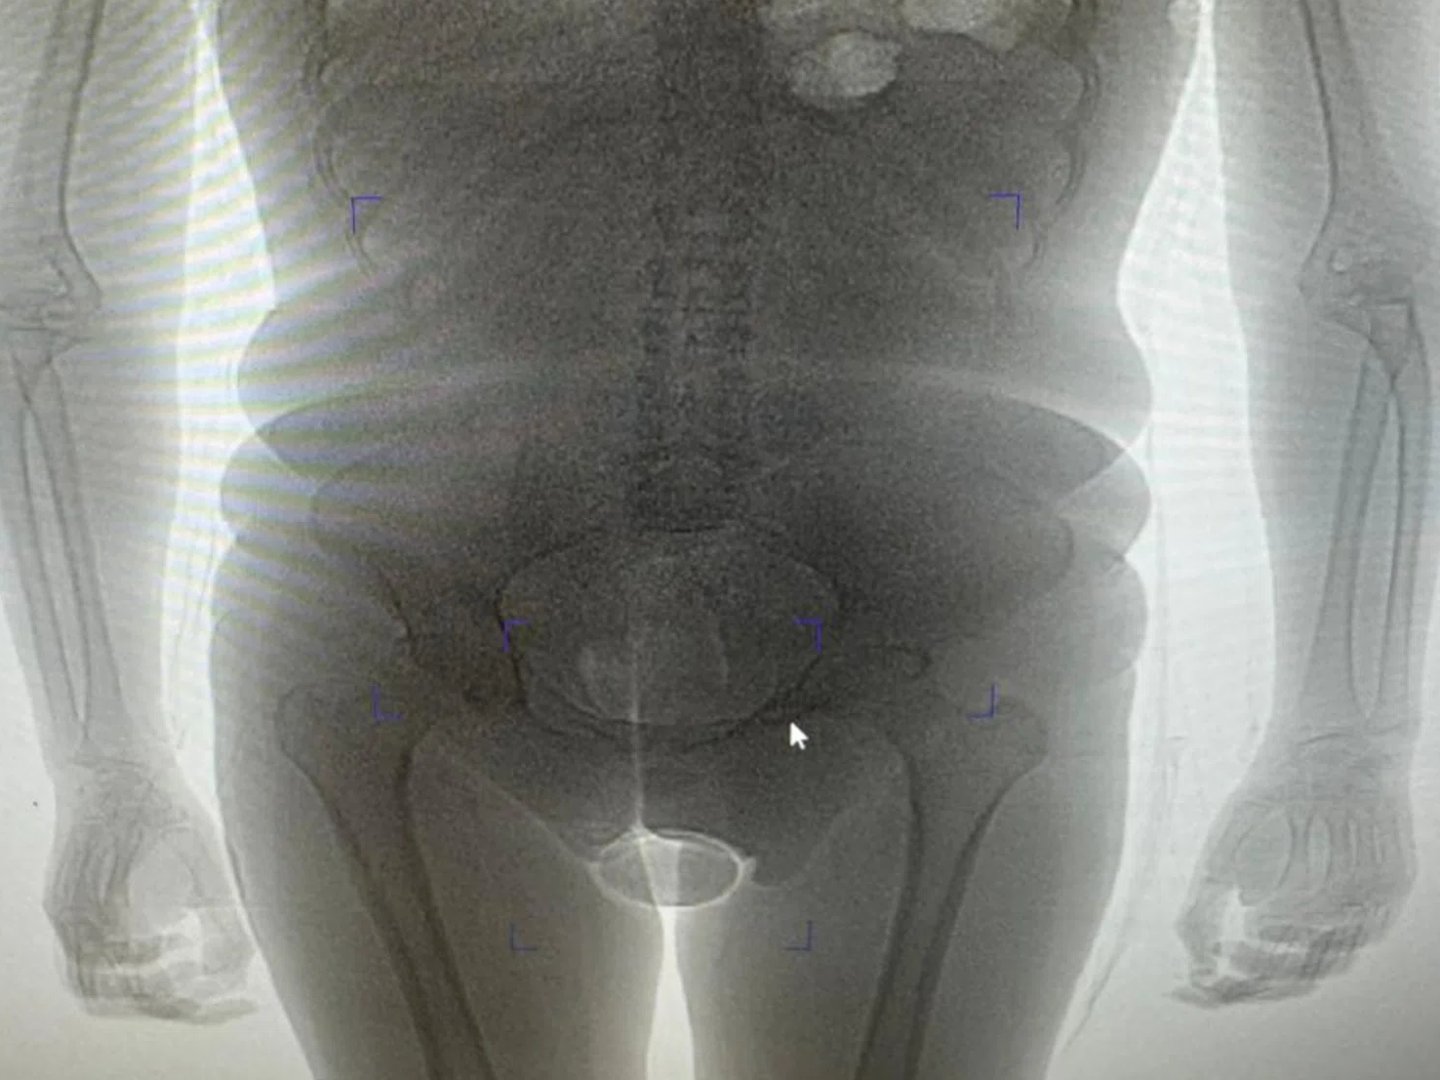

Сотрудники таможенного поста аэропорта Домодедово задержали гражданку Бразилии, подозреваемую в попытке незаконного ввоза наркотиков внутриполостным способом. По данным ведомства, 22-летняя пассажирка, прибывшая рейсом из Дубая, была остановлена в «зеленом» коридоре в рамках проведения оперативно-разыскных мероприятий. Об этом для URA.RU сообщила пресс-секретарь Домодедовской таможни Елена Мартынова.

«В результате проведения таможенного досмотра обнаружено два презерватива с порошкообразным веществом внутри, один из которых находился в нижнем белье пассажирки, второй сокрыт внутриполостным способом», — говорится в заявлении пресс-секретаря. Информация есть в распоряжении URA.RU.